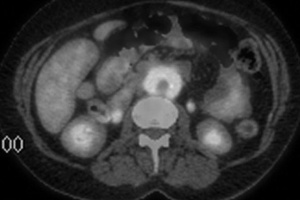

Традиционно для подтверждения диагноза ретроперитонеального фиброза применяется внутривенная урография, при которой могут быть выявлены длинные суженные участки мочеточника и его медиальное отклонение в проекции средней трети, а также гидронефроз. Тем не менее, при ретроперитонеальном фиброзе медиальное отклонение определяется не всегда, в то время как у 20 % людей с нормальными мочевыми путями также выявляется медиальное отклонение мочеточников. В последнее время для уточнения границ поражения при ретроперитонеальном фиброзе применяется компьютерная томография (КТ) и магнитно-резонансное исследование (МРИ), при которых выявляется объемное образование, окружающее полую вену и аорту.